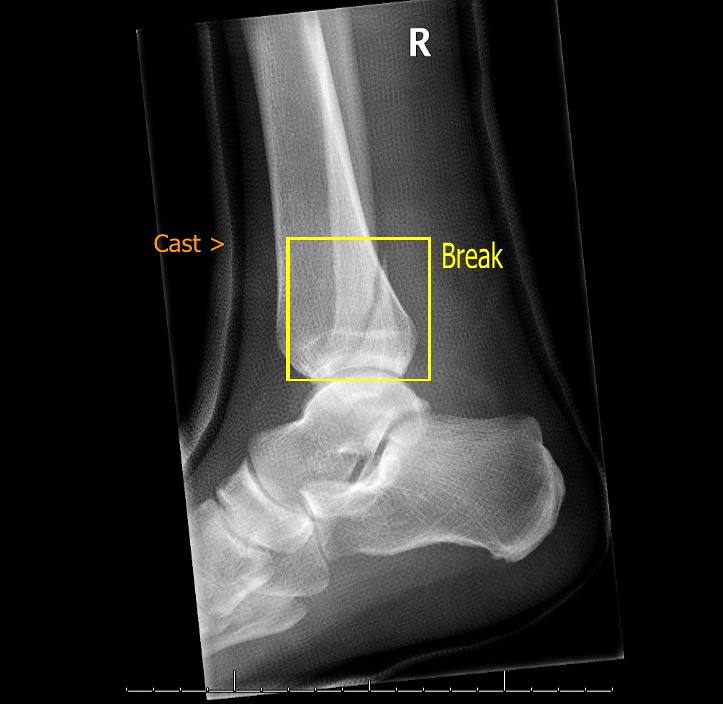

Broken Ankle Xray Xray of my broken ankle. The break is … Flickr Hot Bath Broken Ankle Find out how to tell if your ankle is broken (fractured) and when to get medical advice, plus how a broken ankle is treated and how long it. The ankle joint is made up of the bones in your lower leg (tibia and fibula). Advice after breaking your ankle. Here's how to treat an injured or sprained ankle with ice. Hot Bath Broken Ankle.